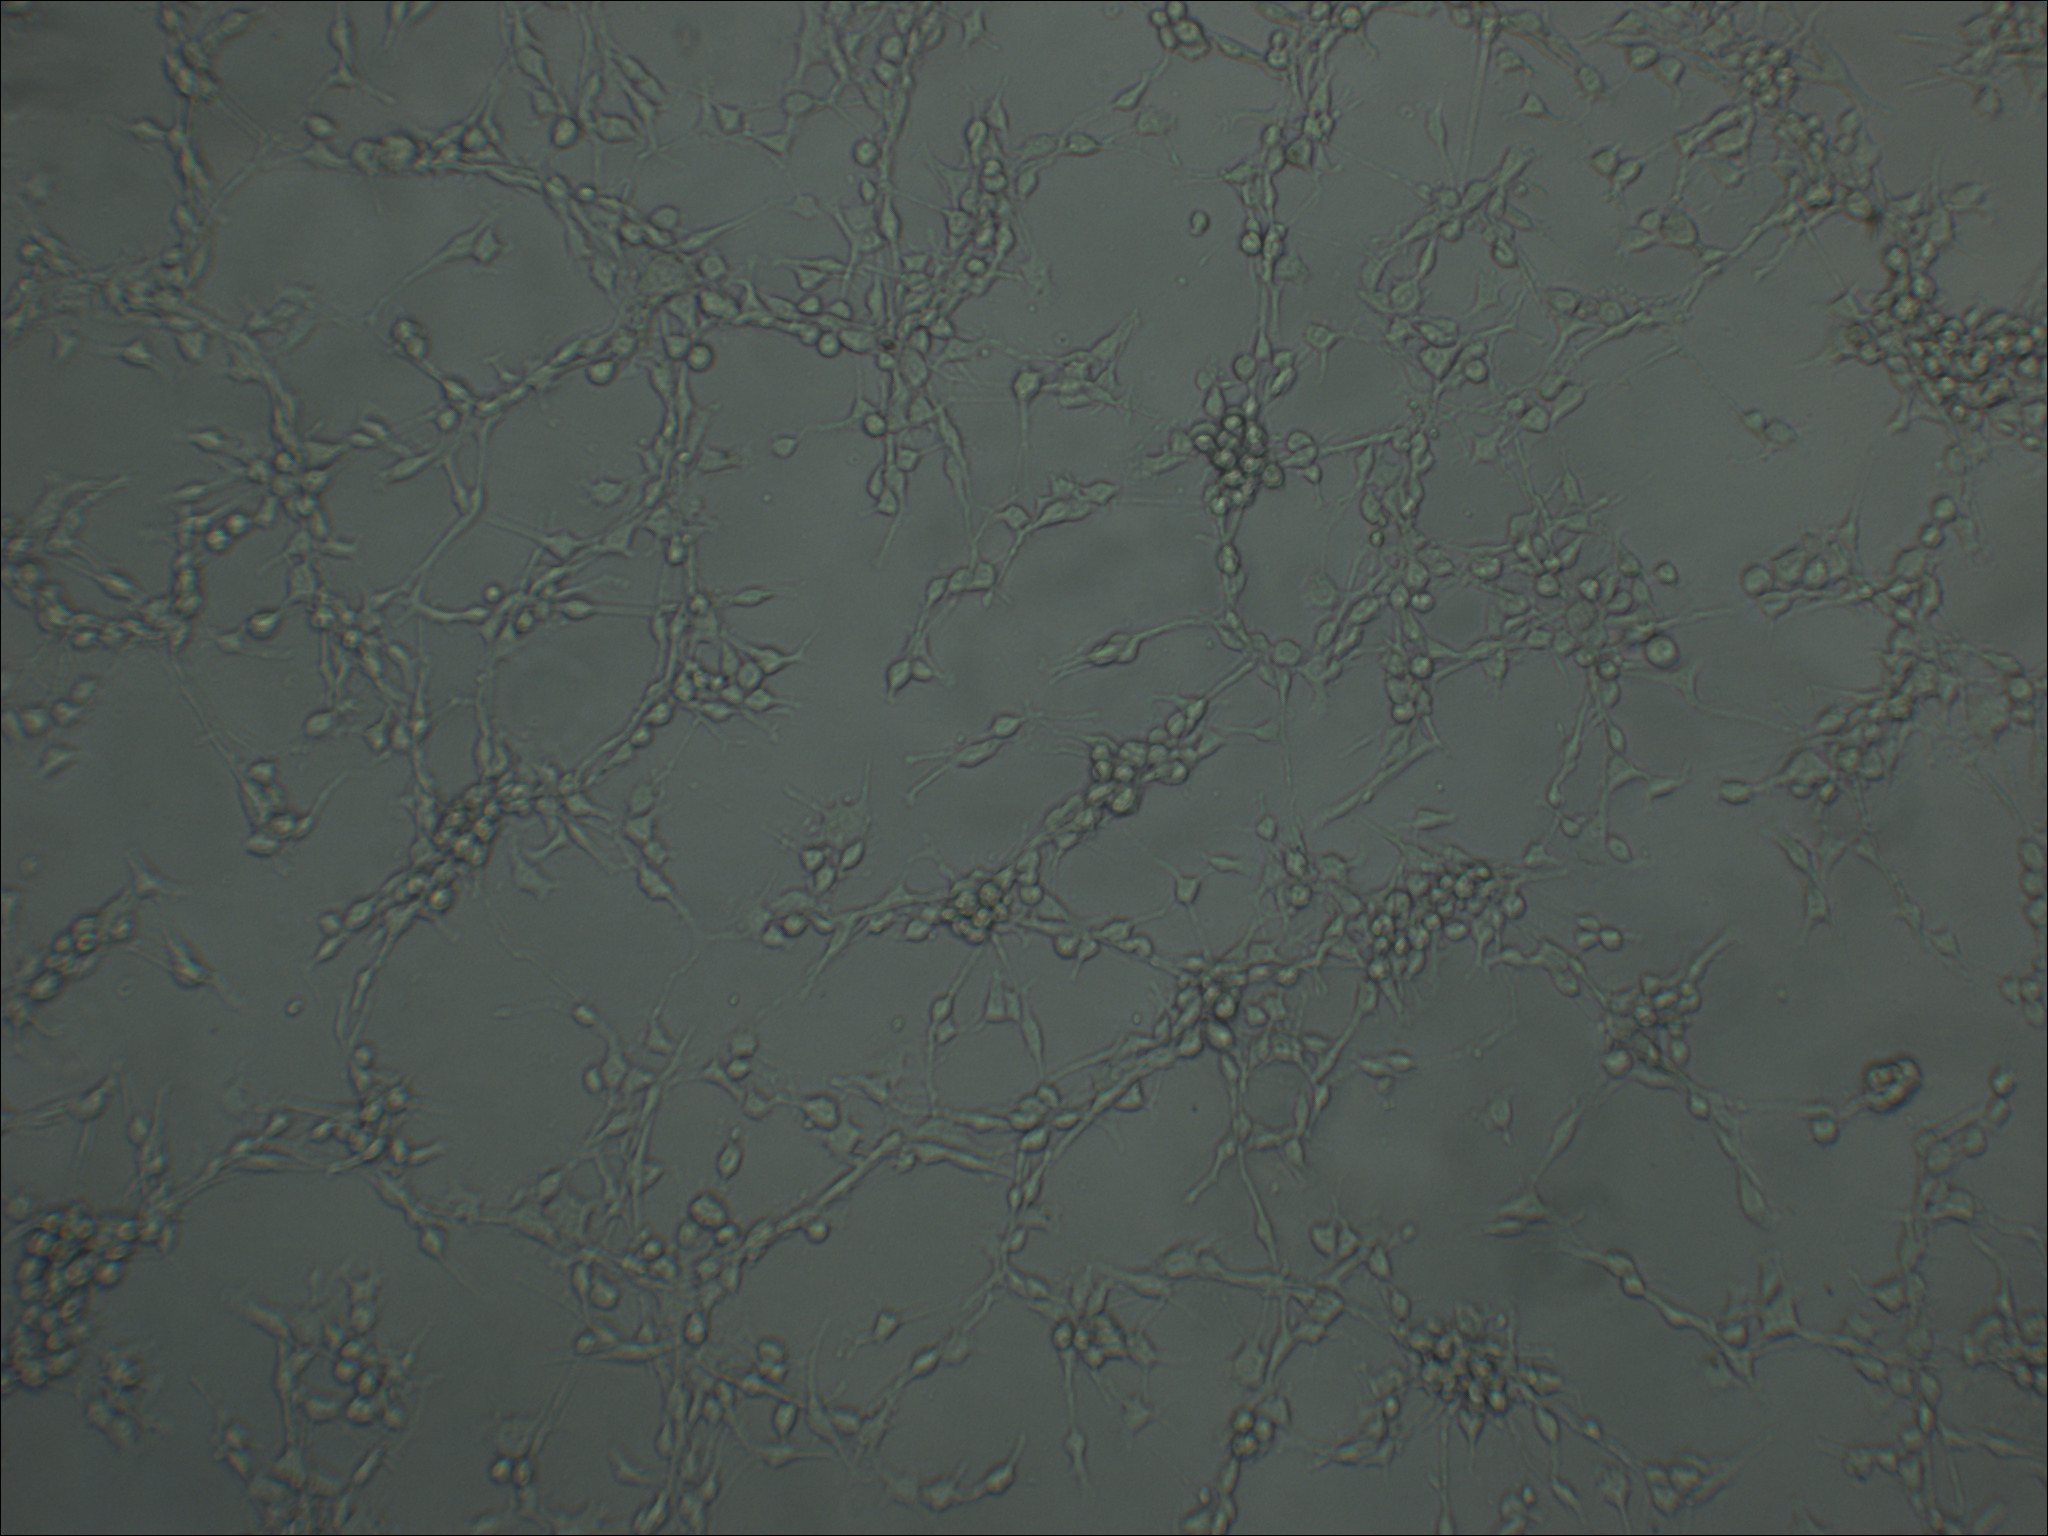

MFC 小鼠前胃癌细胞

形态特征 上皮细胞样

生长特征 贴壁